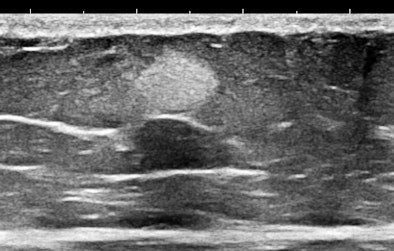

Of course, any of you might say that systemic mastocytosis is such a rare occurrence that one would probably never ever encounter one, but that is probably only true with fully and classically symptomatic cases. We have started looking at abdominal subcutaneous fat as part of our scanning routine, and guess what? This may not be such a rare occurrence at all. Here are some 15-MHz abdominal wall images of a 63-year-old hypothyroid woman who previously had a hysterectomy for a precancerous endometrial polyp:

Her history was interesting, with allergies that began in middle age and episodes of flushing during the past five years that she attributed to "hot flashes."